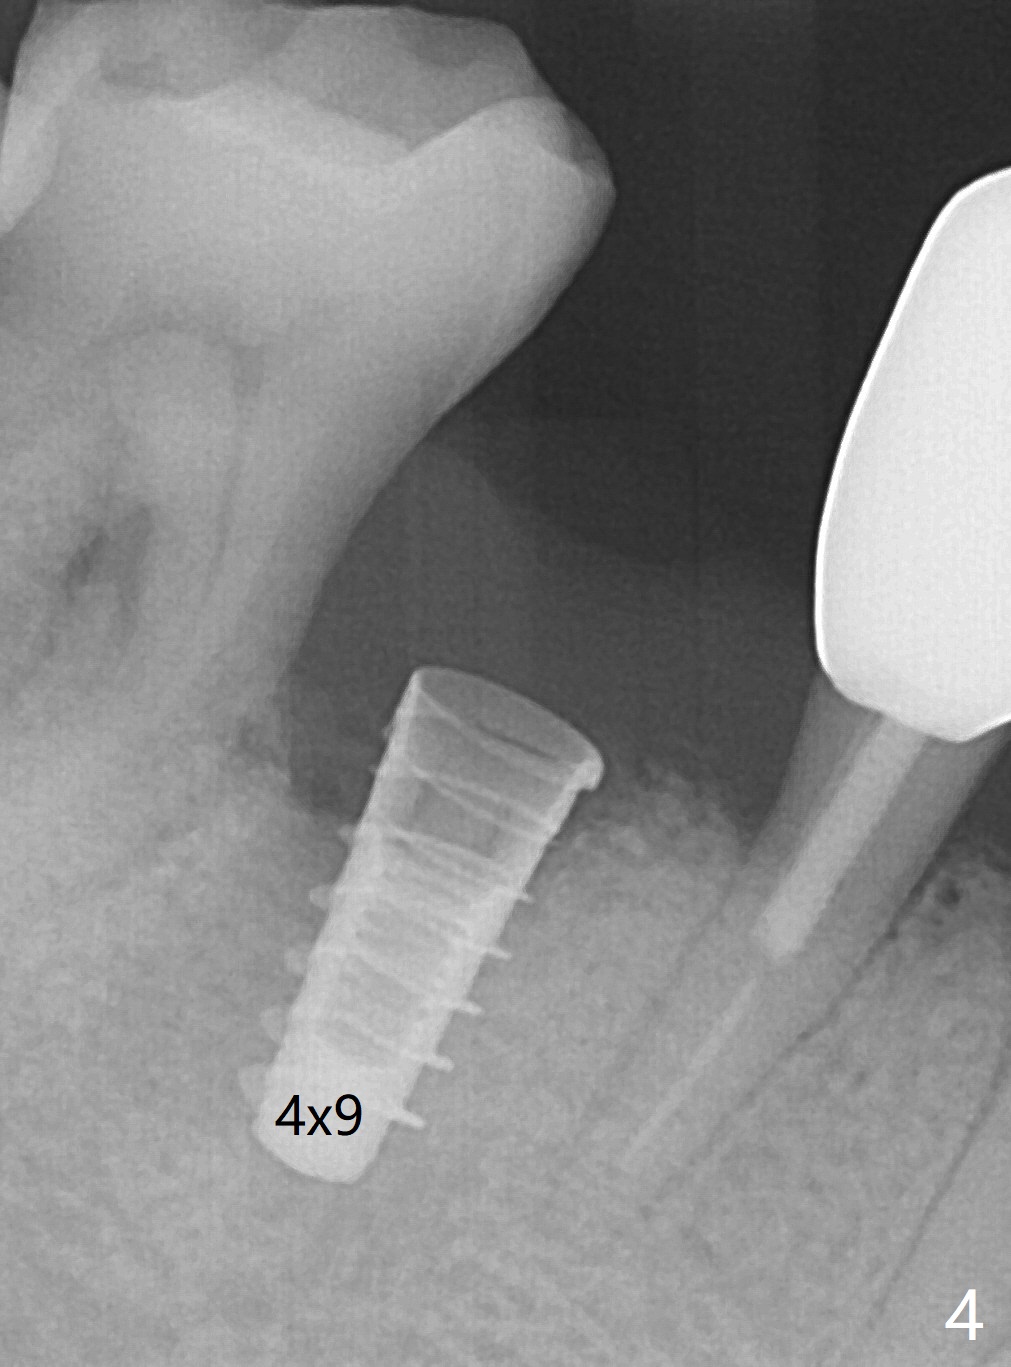

The tooth #29 is easily extracted with granulation tissue attached to the apex (Fig.1,2). The buccal plate is low. Initial osteotomy is established in the mesial slope of the socket for 13 mm subgingival (Fig.3 red dashed line). After adjustment of the osteotomy position and use of Magic Drills 2.8 and 3.3 mm for 15 mm subgingival, a 4x9 mm dummy implant is placed 2 mm subgingival (Fig.4). Final implant (Fig.5: 4x9 mm; red dashed line: socket) is placed 4 mm subgingival (supracrestal buccal; infracrestal lingual); Vanilla graft placed buccodistal (*). With placement of a 4.5x5.7(4) mm abutment (Fig.5), an infraocclusal immediate provisional (Fig.6 P) is fabricated to maintain the interdental papillae. One month later, the abutment dislodges. The patient insists upon no provisional so that he can masticate on the right side, since there is no functional molars on the left side. The implant appears to have osteointegrated 5 months postop (Fig7). The crown is loose 2.5 months post cementation (8.5 months postop); there is bone loss around the implant (Fig.8 *). Vanilla graft is placed after implant removal (Fig.9); in fact the neighboring teeth also have mobility (including periapical radiolucency at #30 (Fig.9 *)).